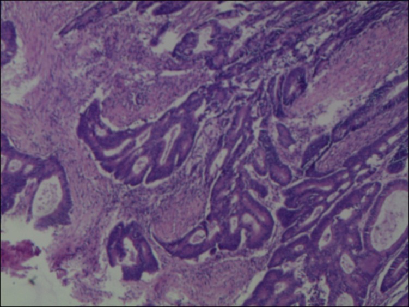

(盆腔肿物)约15X10X3cm,切面灰白,质脆,镜下:可见卵巢结构,其内见腺癌浸润。免疫组化:癌细胞CK20(+),CK(+),CDX-2(+),M-CEA(+),Villin(+),TTF-1(-),CK7(-)。符合直肠腺癌卵巢转移。